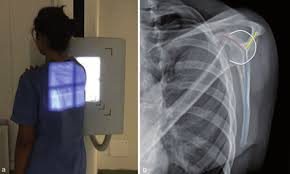

[일반촬영] 어깨뼈(scapula) 전후방향, 측방향 촬영법

어깨뼈(scapula) 검사방법중에는 전후방향(AP projection), 측방향(Lateral projection)촬영 방법이 있으며

우선 전후방향(AP projection) 촬영방법을 먼저 보겠습니다.

어깨뼈(scapula) 전후방향촬영법(AP projection)

어깨뼈(scapula) 방향촬영법(Lateral projection)

출처: Mattioli 1885 Journals

어깨뼈(scapula)의 측면상이 나타나며 어깨뼈몸통(body)의 골격이 가장 잘 보입니다.